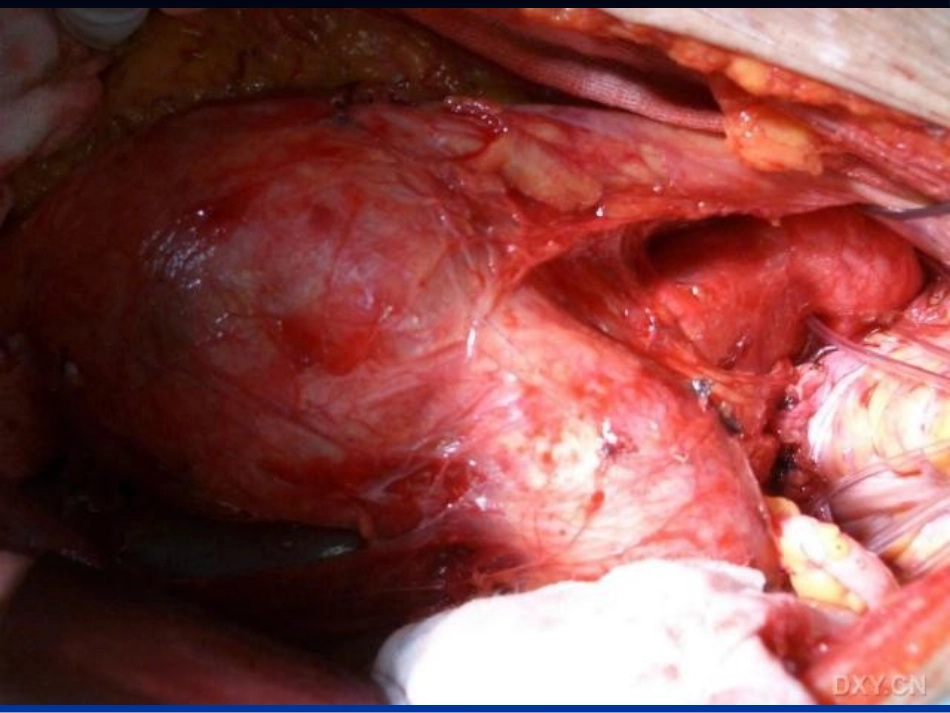

腹主动脉瘤人工血管置换术的麻醉腹主动脉瘤人工血管置换术的麻醉石景辉腹主动脉瘤(abdominalaortaeneurysm.AAA)腹主动脉瘤切除手术步骤腹主动脉瘤切除手术步骤游离瘤体近端及远端及双髂总动脉以备置阻断钳。游离瘤体近端及远端及双髂总动脉以备置阻断钳。瘤体前壁剖开,取出瘤体内淤血、血栓、机化物瘤体前壁剖开,取出瘤体内淤血、血栓、机化物和胆固醇等,结扎腰动脉及骶髂动脉开口和胆固醇等,结扎腰动脉及骶髂动脉开口切断主动脉、髂动脉前壁,选择尺寸合适的人工切断主动脉、髂动脉前壁,选择尺寸合适的人工血管进行移植血管进行移植分别进行主动脉和人工血管、左右髂总动脉与人分别进行主动脉和人工血管、左右髂总动脉与人工血管端端吻合工血管端端吻合腹主动脉人工血管移植完成后,用原动脉瘤壁连腹主动脉人工血管移植完成后,用原动脉瘤壁连续缝合包绕人工血管。缝合后腹膜使瘤体及其缝续缝合包绕人工血管。缝合后腹膜使瘤体及其缝线、吻合口与十二指肠及空肠完全隔开,关腹手线、吻合口与十二指肠及空肠完全隔开,关腹手术结束术结束腹主动脉瘤手术特点腹主动脉瘤手术特点患者多伴全身动脉硬化而导致重要器官功患者多伴全身动脉硬化而导致重要器官功能的损害和异常能的损害和异常血管手术本身对心血管、脑、肾及代谢待血管手术本身对心血管、脑、肾及代谢待功能造成较大的影响,功能造成较大的影响,术中阻断和开放主动脉,可引起血流动力术中阻断和开放主动脉,可引起血流动力学剧烈波动及相应器官脏器不同程度缺血学剧烈波动及相应器官脏器不同程度缺血性损害性损害术后并发症和病死率较高术后并发症和病死率较高腹主动脉瘤切除人工血管置入术麻醉腹主动脉瘤切除人工血管置入术麻醉麻醉原则麻醉原则11、控制高血压、心动过速,以免加重出血、、控制高血压、心动过速,以免加重出血、心肌缺血及瘤体破裂。心肌缺血及瘤体破裂。22、利用调节液体量和药物作用,预防和纠、利用调节液体量和药物作用,预防和纠正腹主动脉阻断、开放造成的血流动力学正腹主动脉阻断、开放造成的血流动力学波动及并发症。波动及并发症。麻醉前评估与准备麻醉前评估与准备进行全面检查,除常规外要进行超声心动及肺功进行全面检查,除常规外要进行超声心动及肺功能检查,了解心肺功能。能检查,了解心肺功能。同位素肾图:了解肾功能同位素肾图:了解肾功能冠心病患者做心肌核素显像,必要时行冠造,了冠心病患者做心肌核素显像,必要时行冠造,了解心肌供血情况。解心肌供血情况。术前使用术前使用ββ受体阻滞药,减少缺血引起的心率增受体阻滞药,减少缺血引起的心率增快,对稳定血流动力学有一定作用。快,对稳定血流动力学有一定作用。高血压病人术前将血压控制在正常或接近正常水高血压病人术前将血压控制在正常或接近正常水平,降压药物服至术晨。平,降压药物服至术晨。术前禁烟,将有利于术后减轻肺部并发症。术前禁烟,将有利于术后减轻肺部并发症。麻醉方法麻醉方法全身麻醉全身麻醉11、术前用药:、术前用药:消除焦虑紧张,减少应激反应。消除焦虑紧张,减少应激反应。吗啡吗啡0.1mg0.1mg//KgKg、哌替啶、哌替啶11--2mg2mg//KgKg安定安定0.15mg0.15mg//KgKg、东莨菪碱、东莨菪碱0.20.2--0.3m0.3mgg/次/次22、术中监测、术中监测::心电图、有创动静脉压、动脉血气、末梢心电图、有创动静脉压、动脉血气、末梢血氧饱和度、重症可放置肺动脉漂浮导管、血氧饱和度、重症可放置肺动脉漂浮导管、经食道二维超声心动图。经食道二维超声心动图。33、麻醉诱导:、麻醉诱导:注意减少气管插管时的应激性高血压及快注意减少气管插管时的应激性高血压及快速心律失常,同时也要避免过度心血管抑制。速心律失常,同时也要避免过度心血管抑制。诱导药物:诱导药物:咪唑安定咪唑安定0.10.1--0.2mg0.2mg//KgKg异丙酚异丙酚0.50.5--1.51.5mgmg//KgKg依托咪酯依托咪酯0.3mg0.3mg//KgKg芬太尼芬太尼22--55μμgg//KgKg44、麻醉维持:、麻醉维持:全凭静脉、静吸复合均可采用。据病人年全凭静脉、静吸复合均可采用。据病人年龄、全身...